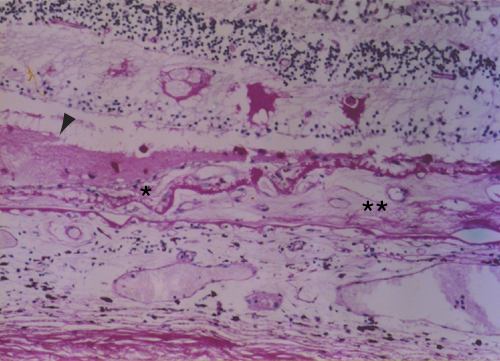

Figure 18. Choroidal neovascularization

A. A two-component, 100 µm maximal thickness, disciform scar with a small subretinal component (single asterisk) and a small area of serous detachment of the macula (arrowhead). There is moderate to total loss of the photoreceptor cell layer over the scar, which is most marked over the thicker intra-Bruch's membrane component (double asterisk). (periodic acid-Schiff; x35).